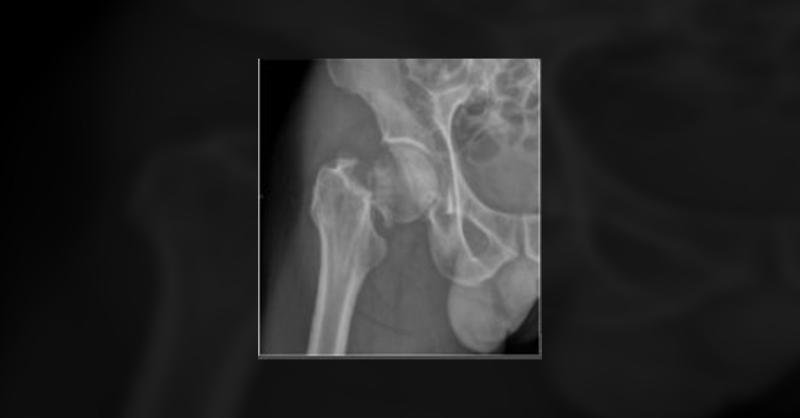

Direct Anterior Approach with Femoral Neck System for Irreducible Displaced Femoral Neck Fractures

Femoral neck fractures (FNFs) in patients under the age of 50 years account for less than 5% of all hip fractures and are typically the result of a high-energy event. Managing FNFs in young patients, particularly displaced fractures, presents a formidable clinical challenge. Internal fixation is the consensus approach, with an emphasis on achieving